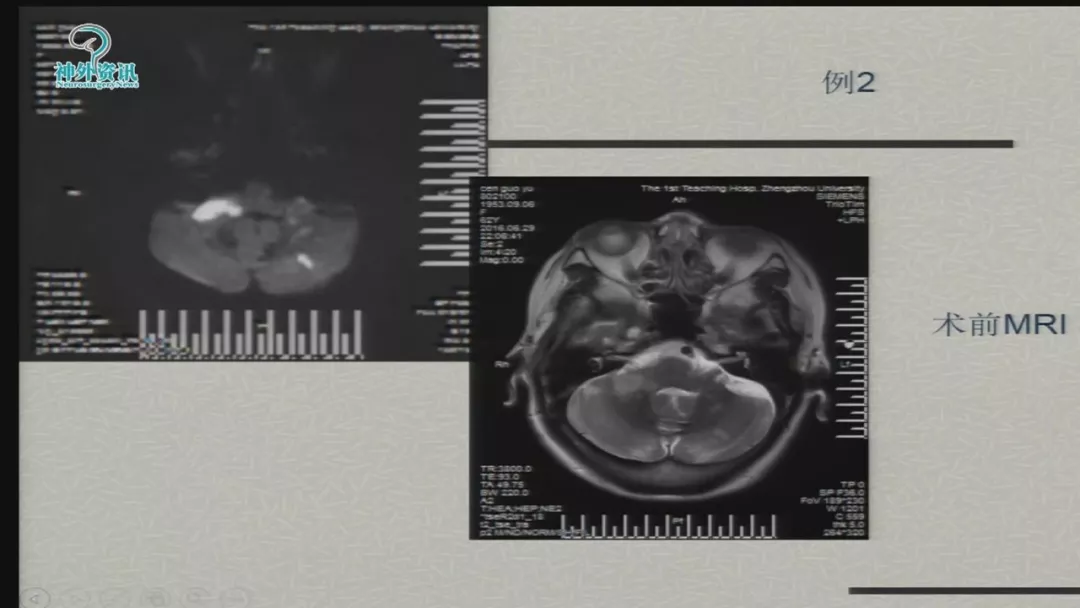

今天为大家分享的是由郑大一附院徐浩文教授在第七届全国介入医学工程大会上带来的“Neuroform EZ在ICAD治疗中的应用”精彩讲课视频和PPT,欢迎观看!(内容未经讲者审核,不当之处请与我们联系)